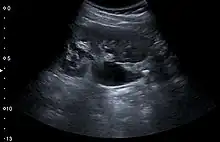

Renal ultrasonography can sometimes be useful, because it gives details about the presence of hydronephrosis, suggesting that the stone is blocking the outflow of urine.[58] Radiolucent stones, which do not appear on KUB, may show up on ultrasound imaging studies. Other advantages of renal ultrasonography include its low cost and absence of radiation exposure. Ultrasound imaging is useful for detecting stones in situations where X-rays or CT scans are discouraged, such as in children or pregnant women.[66] Despite these advantages, renal ultrasonography in 2009 was not considered a substitute for noncontrast helical CT scan in the initial diagnostic evaluation of urolithiasis.[65] The main reason for this is that, compared with CT, renal ultrasonography more often fails to detect small stones (especially ureteral stones) and other serious disorders that could be causing the symptoms.[14]

Renal ultrasonograph of a stone located at the pyeloureteric junction with accompanying hydronephrosis.